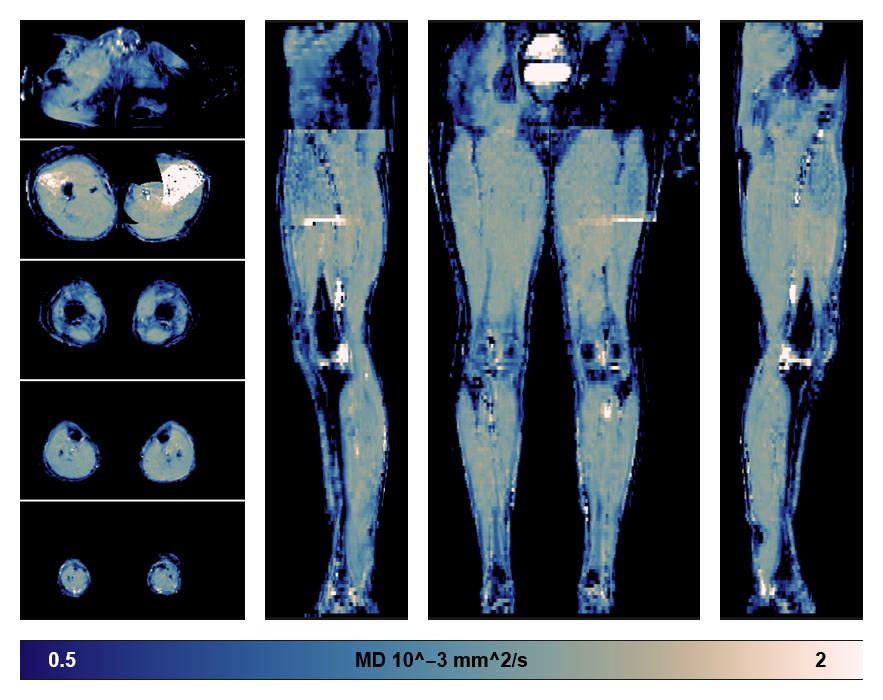

• Mean diffusivity

IVIM corrected whole leg muscle mean diffusivity obtained from diffusion tensor imaging.

• Fractional anisotropy

IVIM corrected whole leg muscle fractional anisotropy obtained from diffusion tensor imaging.